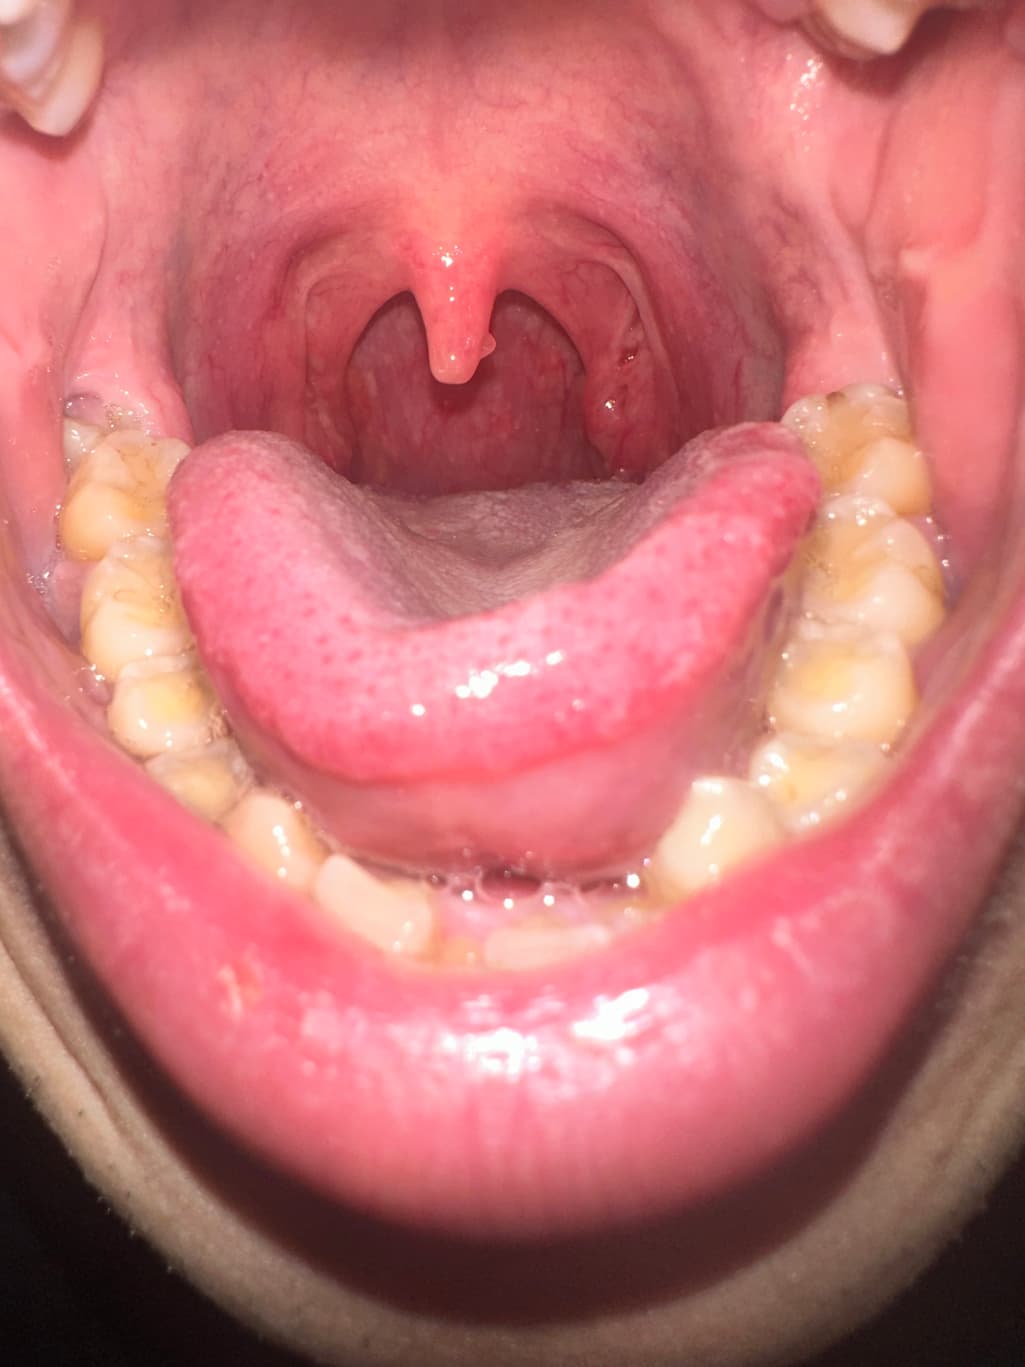

목젖 뒷면 혹이 있어서 확인 부탁드립니다.

올해 1월부터 목젖 뒷면에 혹이 관찰되었습니다.

아래 사진은 지금 사진이고요

점점 위치랑 보이는 면적이 변하는것 같아 문의드립니다.

근처 이비인후과에선 지켜보자고 했는데요.